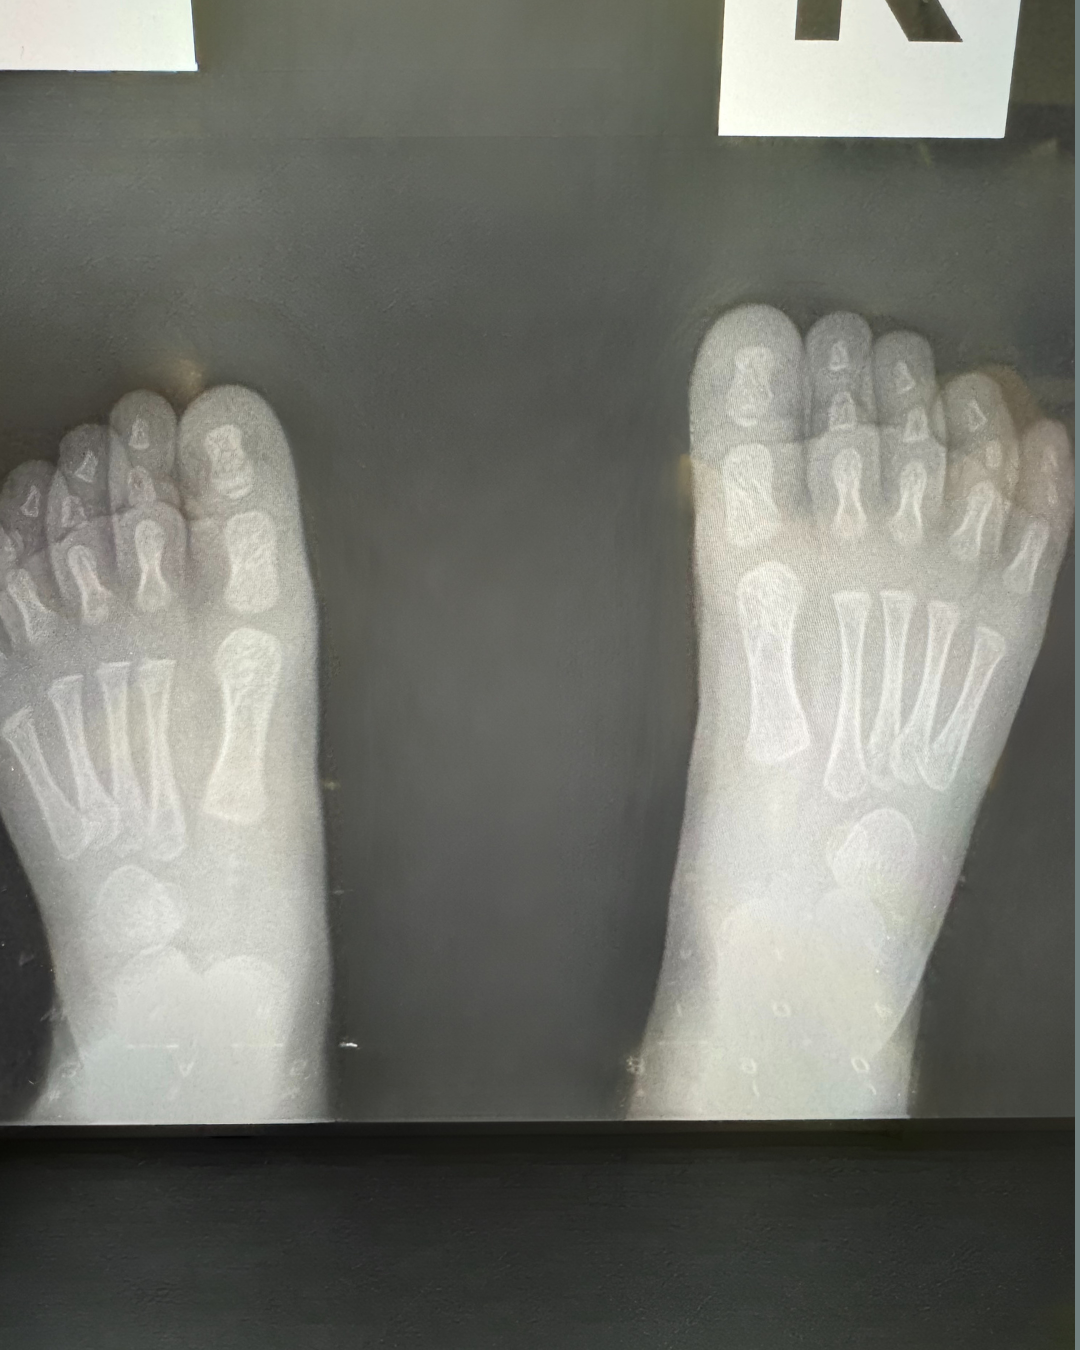

xray of a pediatric foot in a standard ap position. taken by Dr. Dawson in clinic